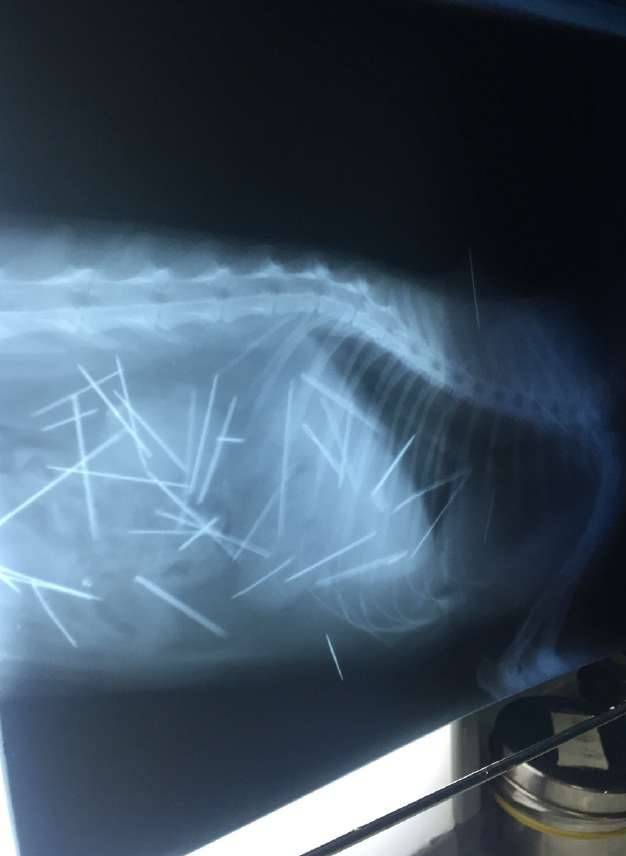

▼这次动物医院连续照了53次X光片,发现猫咪体内有多根细针,有些已经生鏽。

▼其中7根针在皮肤和肌肉、3根针和2根断针在胸腔心脏旁边,30根针在腹腔,其中有4根是插入到左侧肾脏。

▼现在这些针已经开始游离,猫咪很痛苦。医生表示手术也只能取出2/3。

从X光片可以看到,猫咪体内布满密密麻麻的细针,看起来怵目惊心。一年多来,猫咪一直忍受针刺的痛苦,牠无法说话,只能默默承受。在热心人士的帮忙协助下,猫咪终于做完手术,希望牠能够快点好起来,不要再遭遇这样可怕的事。分享出去,让大家都看到吧。